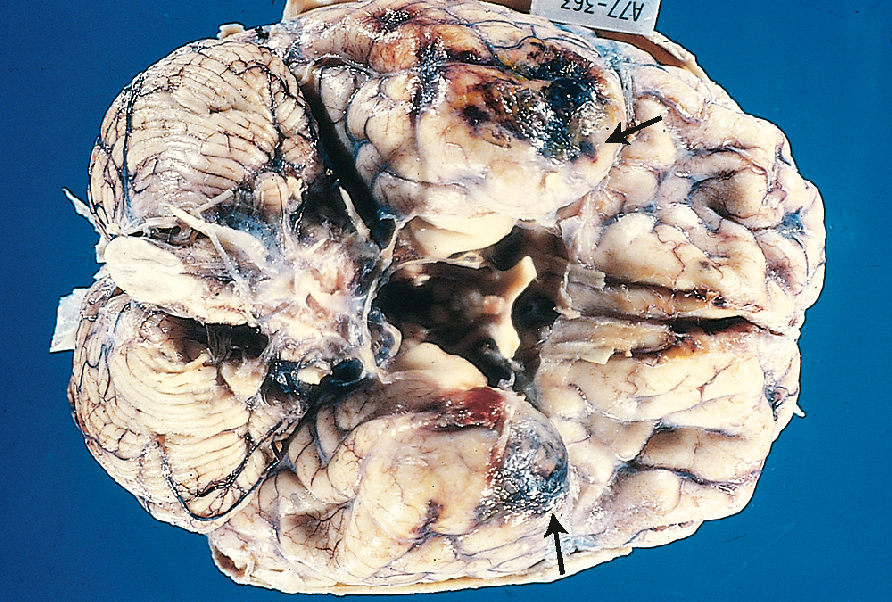

Cerebral contusion occurs when the brain parenchyma strikes fixed portions of the skull during acceleration or deceleration. The forces of compression or shearing can damage the cells and vasculature of the brain and effectively cause bruising of the brain tissue (see Fig 34.9).

While the skull is smooth on the outer surface, within the cranial vault there are many protrusions and ridges, particularly on the base of the vault, which can generate high levels of compression or shearing when brain tissue is forced against them. Flexion and extension of the neck can result in contusions on the opposite side to where the force was originally applied (contrecoup; see Fig 34.10).

The frontal lobe striking the frontal bone and the temporal lobe striking the sphenoid bone are the two most common locations for cerebral contusions (Mandavia et al., 2011). Frontal lobe contusions are typically characterised by agitation, confusion, repetitive questioning, impaired short-term memory and aggressiveness that often requires physical and chemical restraint. These cerebral contusions, especially frontal or temporal, are often characterised by a high incidence of posttraumatic seizures and neurosurgeons often recommend routine prophylactic treatment with anticonvulsants for approximately 7 days post-injury (Mandavia et al., 2011).